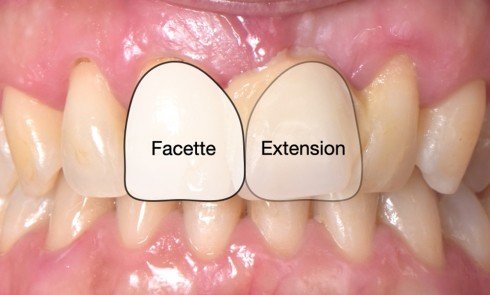

L’amélogenèse imparfaite est le nom donné à un groupe hétérogène de pathologies caractérisées par un défaut inné du développement de l’émail affectant toutes les dents des deux dentures. Ce sont des maladies génétiques dont l’origine est la mutation d’un gène impliqué dans l’amélogenèse. À ce jour, plus de 200 mutations différentes ont été identifiées, ce qui explique des phénotypes très variés [1]. Selon le stade de la maladie, l’émail est hypoplasique (défaut quantitatif), hypominéralisé, ou hypomature (défauts qualitatifs) : il est fin, fragile, tâché ou dyschromique. L’intensité des défauts peut être légère (forme frustre) ou très sévère, allant jusqu’à une absence totale d’émail. Son aspect est altéré par des dyschromies, fractures ou irrégularités de surface (fig. 1-4).